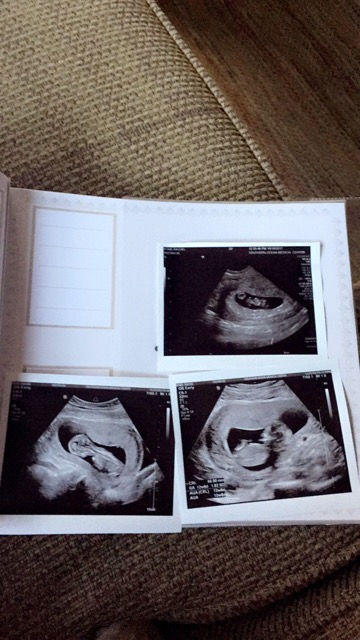

boy or girl?

top from 7 weeks transvaginal, bottom 13 weeks abdominal. anyone wanna take a guess on gender??